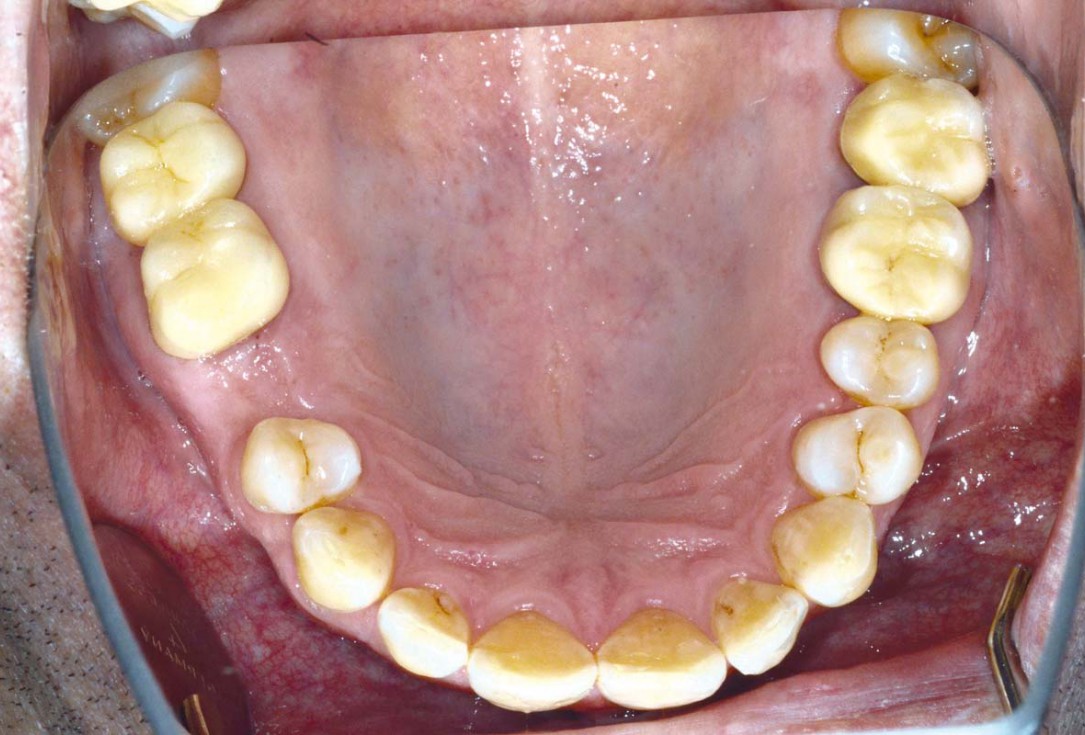

03/06 - Healing three months post-operative.Socket preservation with cerabone® - Dr. P. Kämmerer